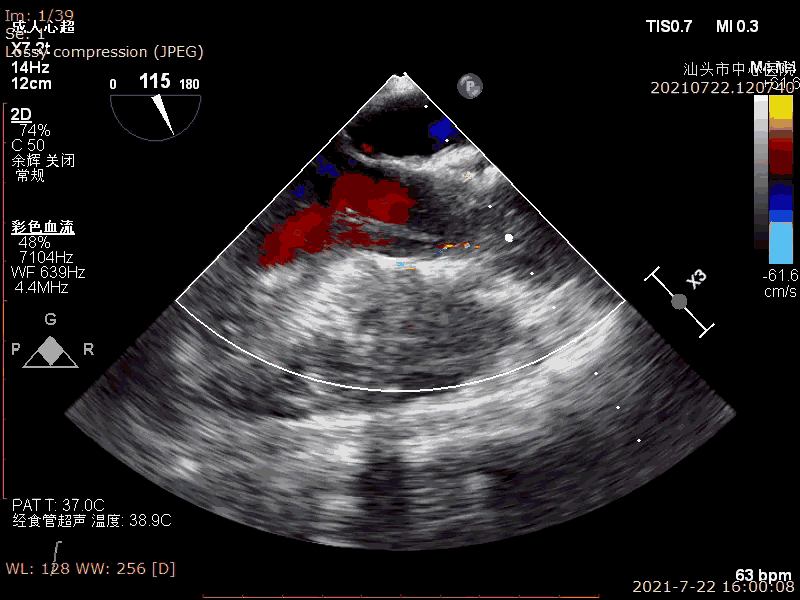

术前超声

术后超声